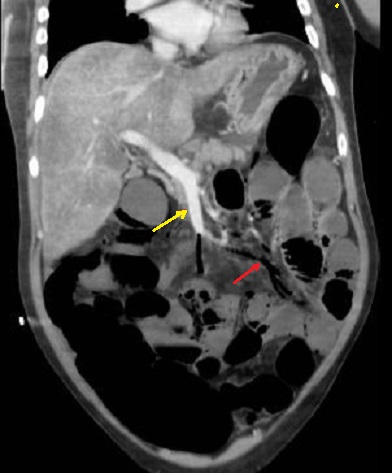

- Aspect radiologique de

ischemie mesenterique veineuse de l'intestin : Image

de thrombose d'une partie de la veine mesenterique

superieure et image oedemateuse , aero-mesenterique

du mesentere

en voyait si net ( fleche rouge ) . Aspect de

defaut

de rehaussement de la paroi de l'intestin peut en

voyait . Image radiologique TDM en coupe coronal ,

phase veineuse |